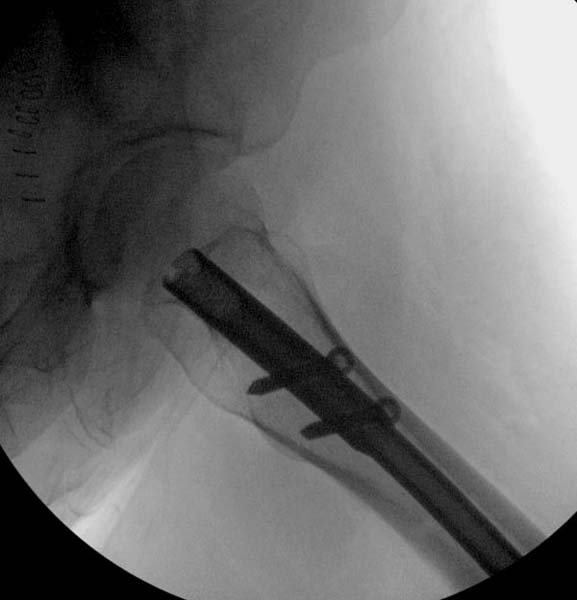

> Больная стабильная после хирургических мероприятии и получив добро,

> приступили к закрытому вправлению таранной кости с укладкой наружного

> фиксатора. Затем укладка больную на бок и открытый остеосинтез